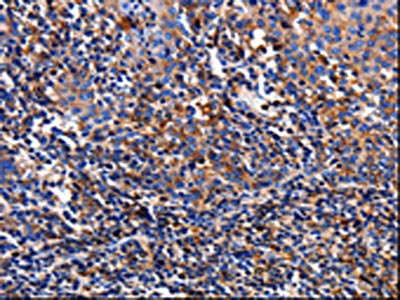

The image on the left is immunohistochemistry of paraffin-embedded Human tonsil tissue using CSB-PA143118(TTR Antibody) at dilution 1/10, on the right is treated with fusion protein. (Original magnification: ×200)